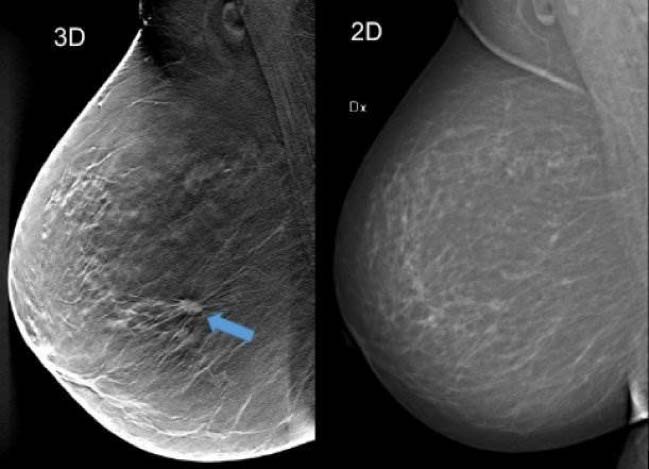

La ricerca tecnologica ha perciò cercato di sopperire a tali limiti della mammografia digitale sviluppando la MAMMOGRAFIA CON TOMOSINTESI.

Si tratta, in pratica di una Mammografia Tridimensionale (3D) ad Alta Definizione.

La TOMOSINTESI è una procedura diagnostica che permette di studiare la mammella ‘a strati’, come la TC; la mammella viene scomposta in tante immagini che poi, sovrapposte, ricostruiscono la figura della mammella nella sua completezza.